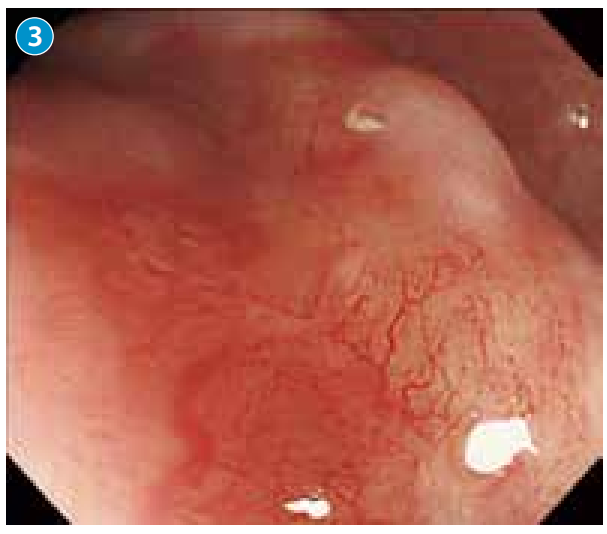

●近距离观察病变顶部凹陷处,见扩张的血管横行、纵行生长,不规则的分支呈网状分布。

●NBI下弱放大观察,顶部呈现较浅但依然可以识别的褐色区域(brownish area),内部为树枝状分布、不规则、缺乏环状的异常血管。